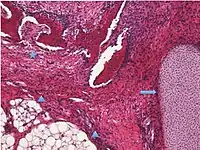

| Germ cell tumor | Mature cystic teratoma | 46.0% | 0.17% to 2%[3] | Cystic, with elements of all 3 germ layers (endoderm, mesoderm and ectoderm).[4] | .jpg.webp) Hair follicles. |